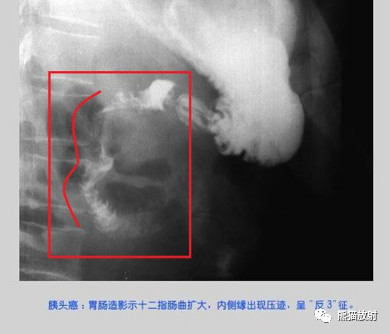

(1)壶腹癌、胰头癌:很早就可侵犯十二指肠内侧壁,致十二指肠圈扩大或(和)十二指肠肠壁双重阴影即双边征,典型者表现为反“3”字征,胃窦大弯受压称“垫征”,而十二指肠癌则很少出现。壶腹癌黄疸出现早。然而壶腹癌和胰头癌均可侵犯十二指肠黏膜,产生与十二指肠癌相同的X线表现而难以鉴别。

图4-9 十二指肠反“3”字征(细箭头)及“垫征”(粗箭头)